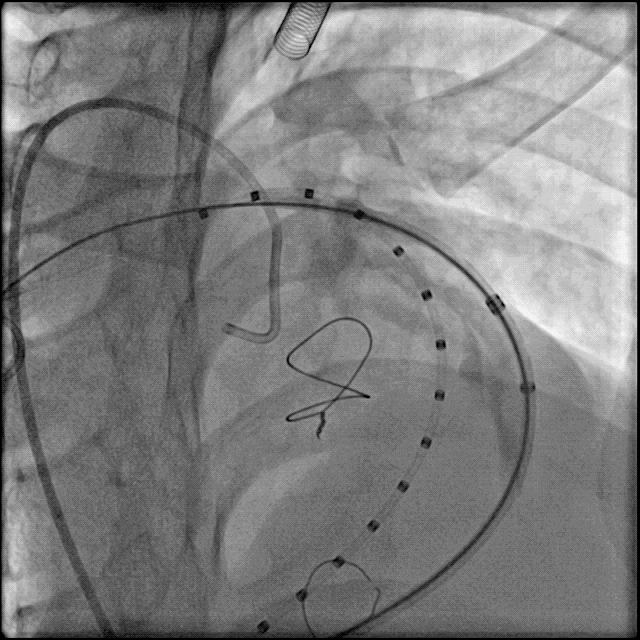

术中肺动脉造影:

重度肺动脉瓣关闭不全,大量返流。

肺动脉造影测量肺动脉内径等参数: